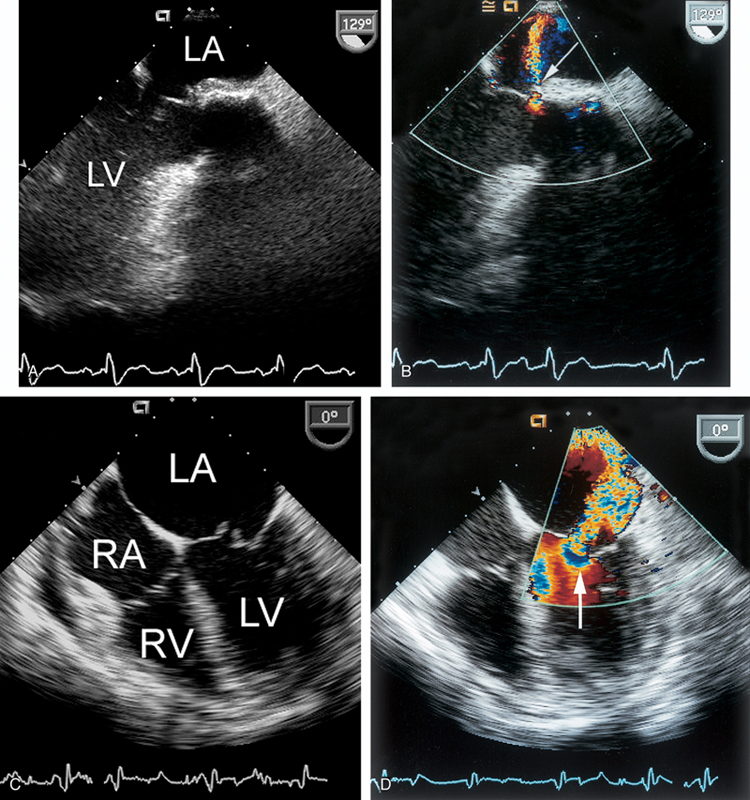

فحوصات تشخيصية لبعض امراض القلب والشرايين التاجية